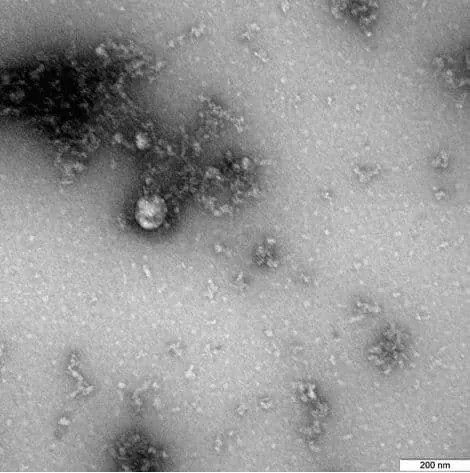

Un equipo de científicos de control de salud pública de Rusia se ha convertido en el primero del mundo en capturar una imagen de la nueva cepa.

“El Centro Estatal de Investigación Vector de Rospotrebnadzor es el primero en el mundo en tomar una fotografía de la cepa de coronavirus del Reino Unido, hallada en un paciente en diciembre de 2020”, señaló el organismo.

De acuerdo con los investigadores, la foto habría sido tomada mediante un microscopio durante un estudio sobre esta nueva variante y sus propiedades, entre las que se incluyen las características estructurales, su expresión en cultivos celulares y los modelos experimentales que usan animales de laboratorio.

De esta forma, la captura microscópica, que corresponde a la primera imagen de esta nueva variante, les puede ayudar a los científicos a conocer más aspectos sobre la cepa británica del coronavirus, que se estima sería un 70 por ciento más contagiosa que las otras variantes del SARS-CoV-2.